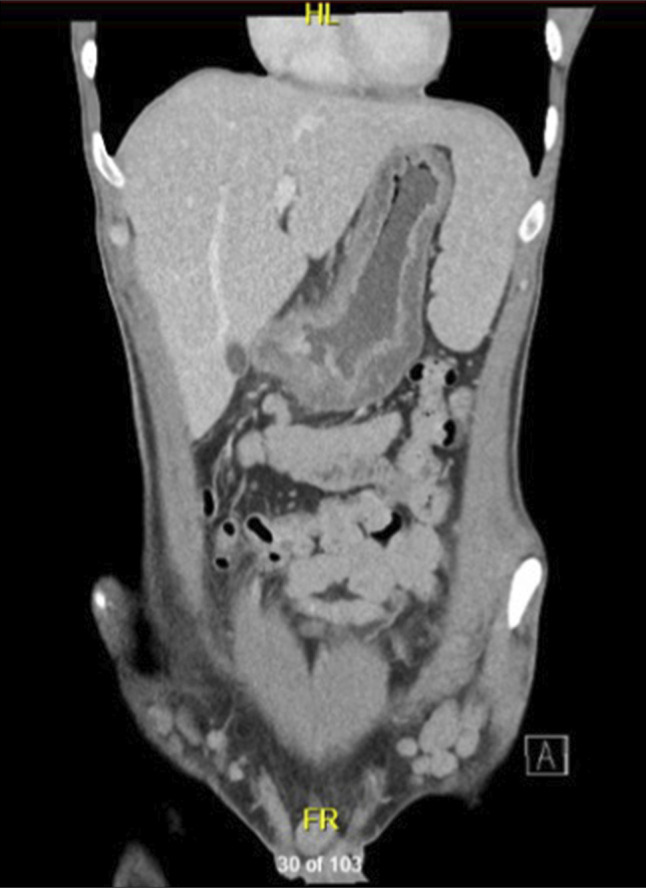

一名患有克罗恩病(CD)的26岁男子在接受抗ox40治疗(罗卡替利单抗)治疗湿疹后出现CD耀斑。这种病变的特征是上胃肠道受累和坏死性肺结节,这是CD的一种罕见的肺部表现。小鼠模型显示抗ox40和抗ox40配体治疗结肠炎的混合效果,抗ox40治疗已在溃疡性结肠炎中进行了试验,但未见明显的临床反应。抗ox40治疗对乳糜泻患者的影响尚不清楚,尽管本病例提示在该人群中使用抗ox40治疗时可能需要谨慎。

A 26-year-old man with Crohn's Disease (CD) presented to hospital with a CD flare after exposure to an anti-OX40 therapy (rocatinlimab) for eczema. This flare was characterized by upper gastrointestinal tract involvement and necrobiotic pulmonary nodules, a rare pulmonary manifestation of CD. Murine models have demonstrated mixed effects of anti-OX40 and anti-OX40 ligand therapies on colitis, and anti-OX40 therapy has been trialed in ulcerative colitis without significant clinical response seen. The impact of anti-OX40 therapies in patients with CD remains unclear, though this case suggests that caution may be required when using anti-OX40 therapies in this population.